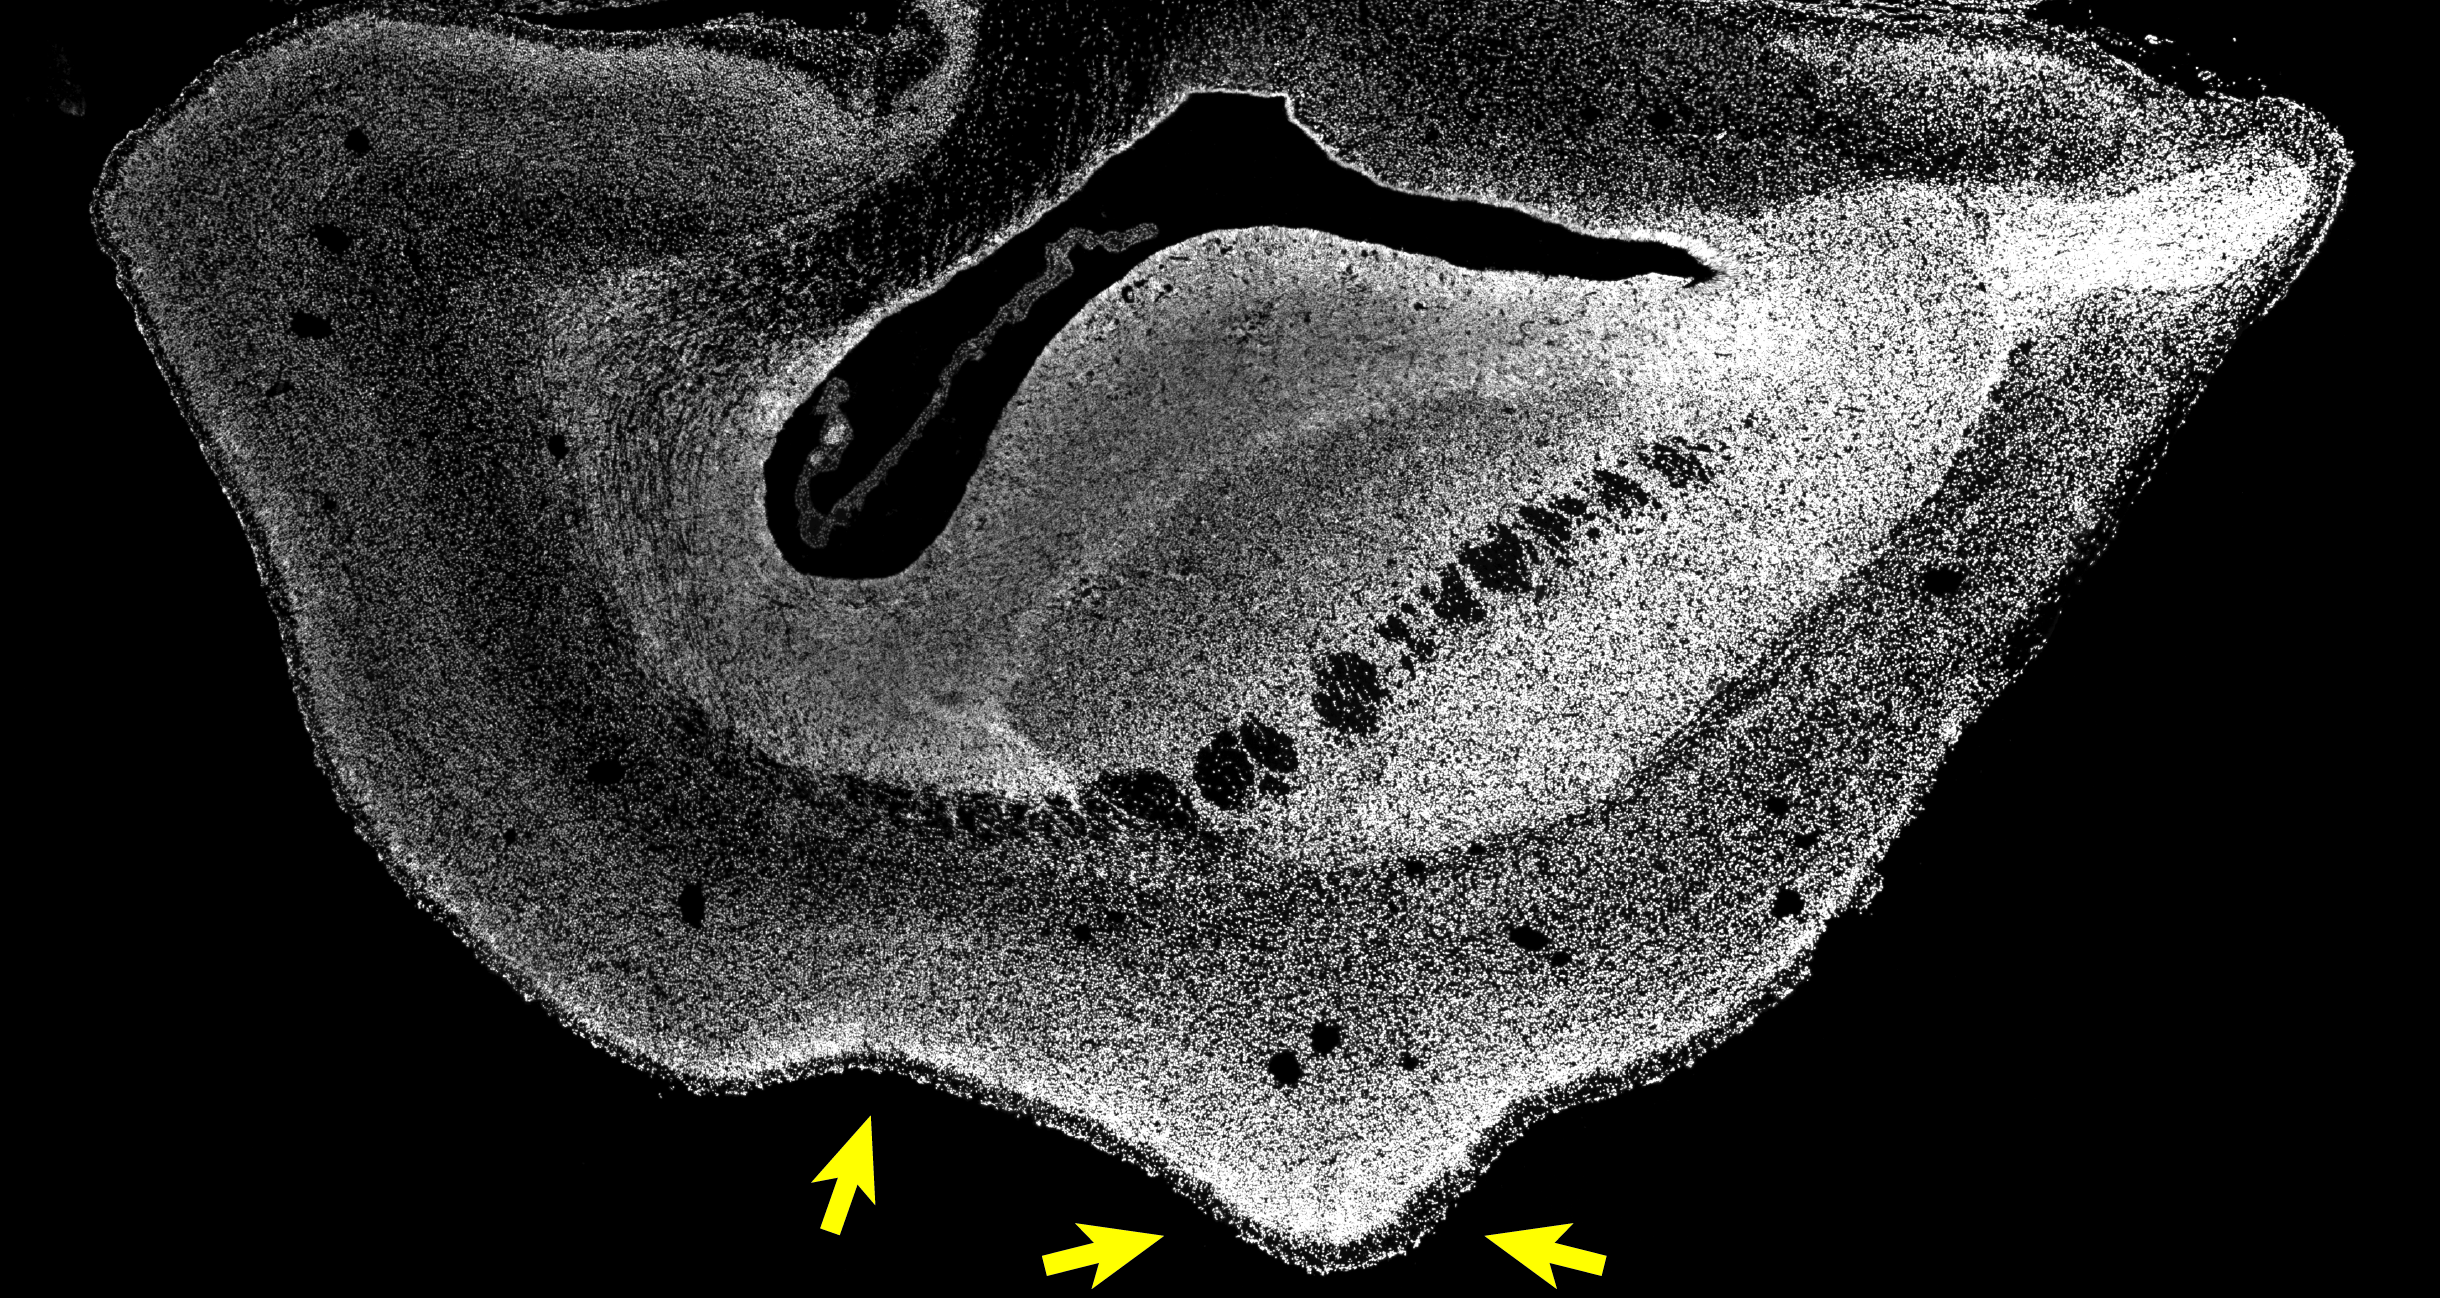

However, it has been unclear until now if the human-specific gene ARHGAP11B would also cause an enlarged neocortex in non-human primates. To investigate this, the researchers in the group of Wieland Huttner teamed up with Erika Sasaki at the Central Institute for Experimental Animals (CIEA) in Kawasaki and Hideyuki Okano at the Keio University in Tokyo, both located in Japan, who had pioneered the development of a technology to generate transgenic non-human primates. The first author of the study, postdoc Michael Heide, travelled to Japan to work with the colleagues directly on-site. They generated transgenic common marmosets, a New World monkey, that expressed the human-specific gene ARHGAP11B, which they normally do not have, in the developing neocortex. Japan has similarly high ethical standards and regulations regarding animal research and animal welfare as Germany does. The brains of 101-day-old common marmoset fetuses (50 days before the normal birth date) were obtained in Japan and exported to the MPI-CBG in Dresden for detailed analysis. Michael Heide explains: “We found indeed that the neocortex of the common marmoset brain was enlarged and the brain surface folded. Its cortical plate was also thicker than normal. Furthermore, we could see increased numbers of basal radial glia progenitors in the outer subventricular zone and increased numbers of upper-layer neurons, the neuron type that increases in primate evolution.” The researchers had now functional evidence that ARHGAP11B causes an expansion of the primate neocortex.